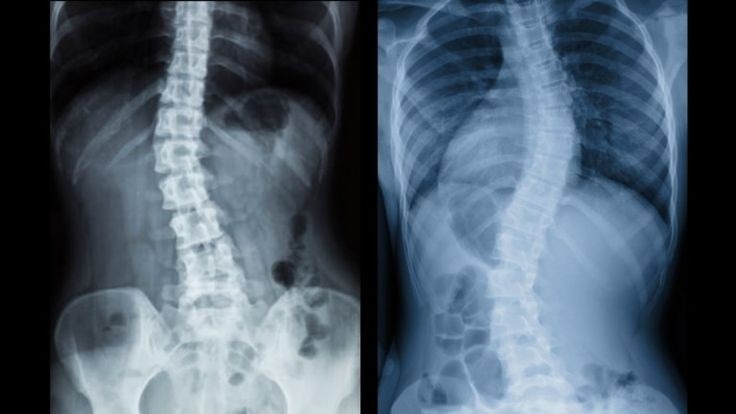

Scoliosis

به هر نوع انحراف جانبی ستون فقرات، اسکولیوز میگن که به دو صورت C و S وجود داره.

(توی نوع C یک قوس و نوع S دو قوس غیر نرمال ایجاد میشه.)

میزان این قوس توی افراد مبتلا به این بیماری متفاوت هست و همین درجهبندی رو ایجاد میکنه.